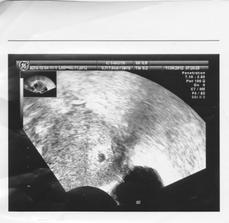

Tehu..3.pokus

autorahoj moje...no neviem,pregnyl už na 9DPO bol snehobiely,i tak sa bojím,lebo tu niekomu ukázal pozitívny testík a potom negatívny..ach jaj,sú to nervy...ja idem v utorok na krv.pocity??- malinko nejaká zmena v prsiach,ale taká malá,že ani neviem,čo,presne,...,žravosť,..a teraz som skoro zaspala za volantom...

ja neviem,je to veľmi slabé...mama test ,dúfam,že nie chybový...v utorok budem vedieť viacej... 🙂